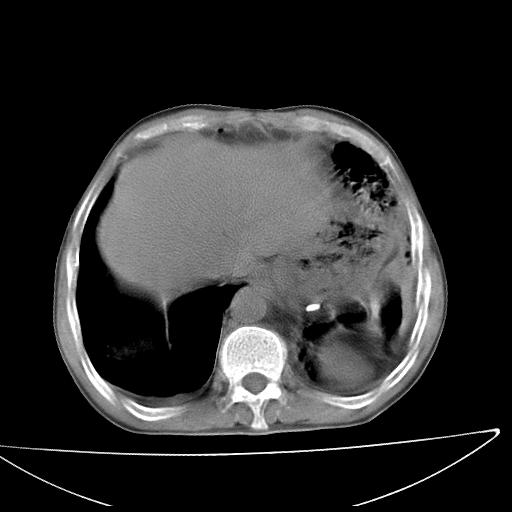

男  70岁,发烧咳嗽4天。盗汗,消瘦。无痰中带血丝,以前有肺tb病史,ct见,双肺tb,左侧胸廓塌陷,左胸膜肥厚粘连。纵隔移位,右侧胸腔积液,大家说说那个心影前左肺舌叶除了肺大炮还有炎症还是干酪性肺炎?有占位吗?我看纵隔淋巴结也大。

是胃,纵膈未见明显肿大淋巴结。